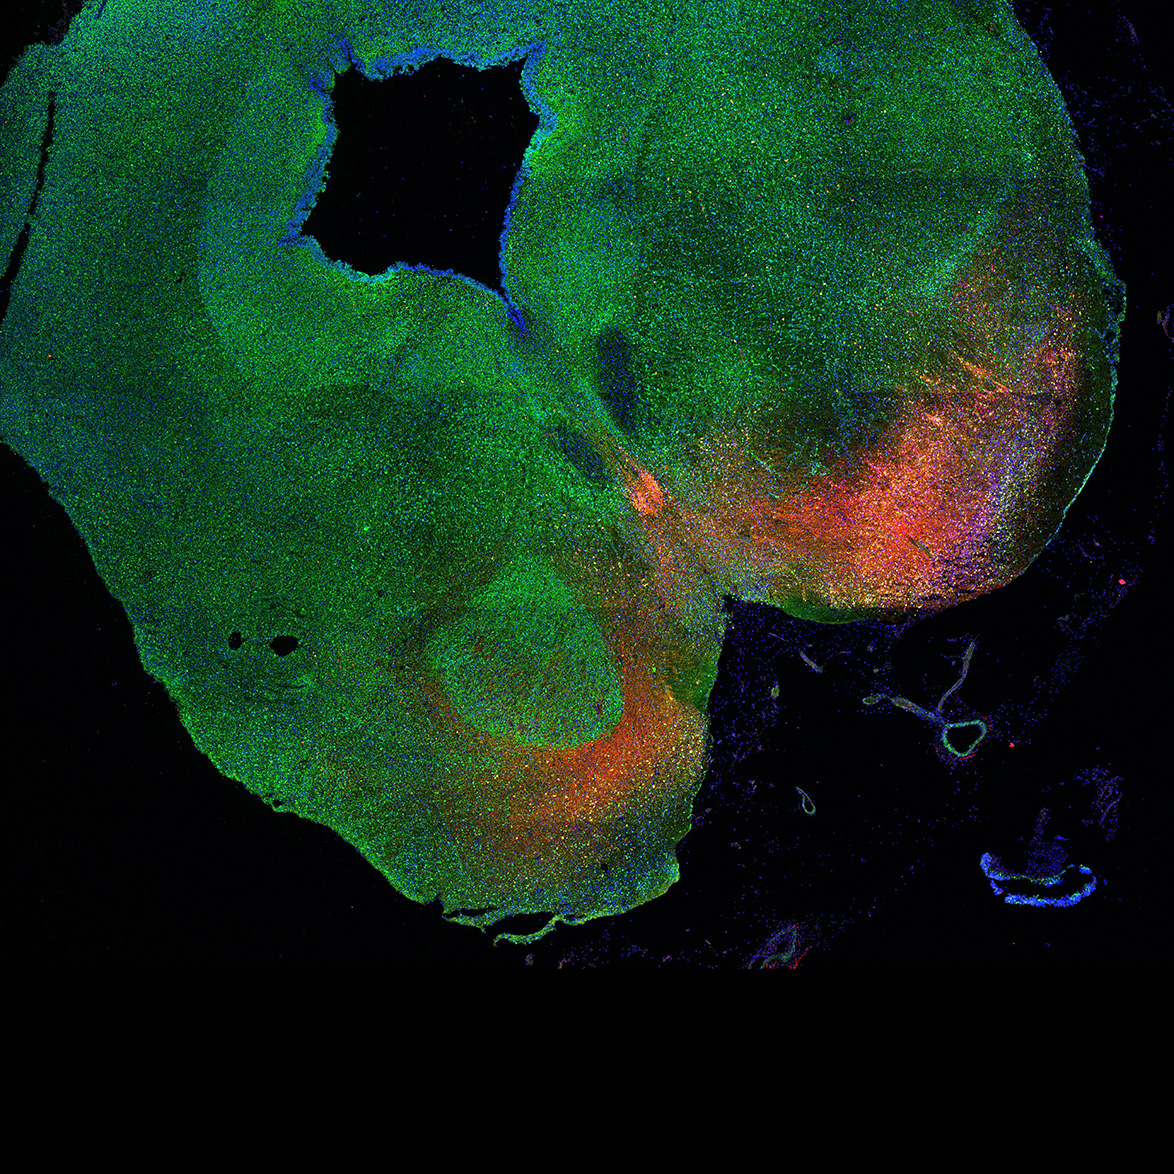

An anatomical analysis of the developing human midbrain from 6 post-conceptional weeks (PCW) to 22 PCW reveals increased tissue complexity, characterized by the emergence of dopaminergic nuclei, as highlighted by immunofluorescence analysis for tyrosine hydroxylase (TH).

Merged

11PCW human midbrain